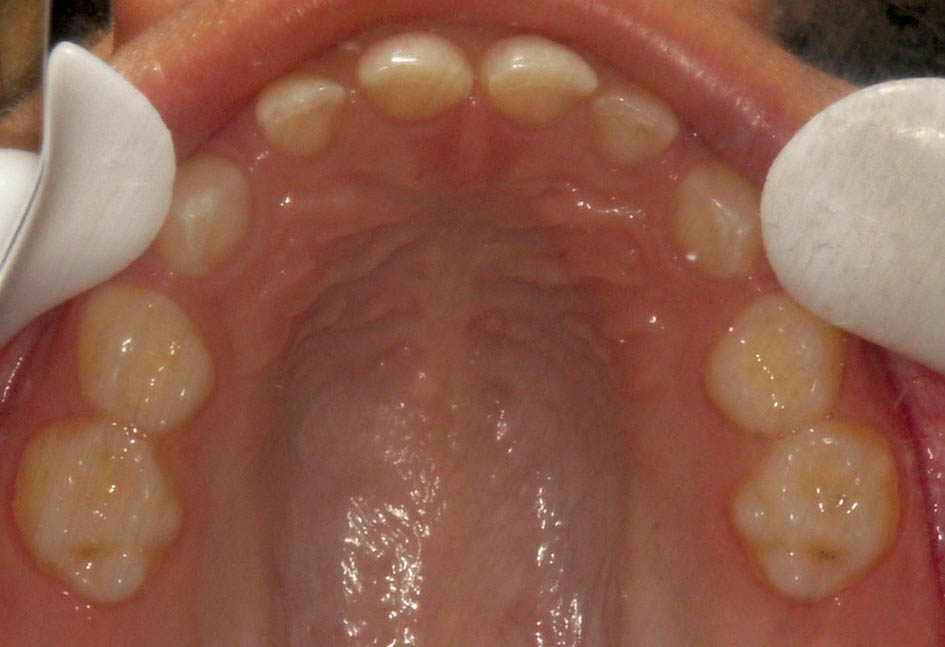

1. بین انسیزورهای شیری بالا حدوداً 4mm (شکل 5-5) و پایین 3mm (شکل 6-5) فضا وجود دارد

شکل 5-5: سایز کوچک انسیزورهای بالا